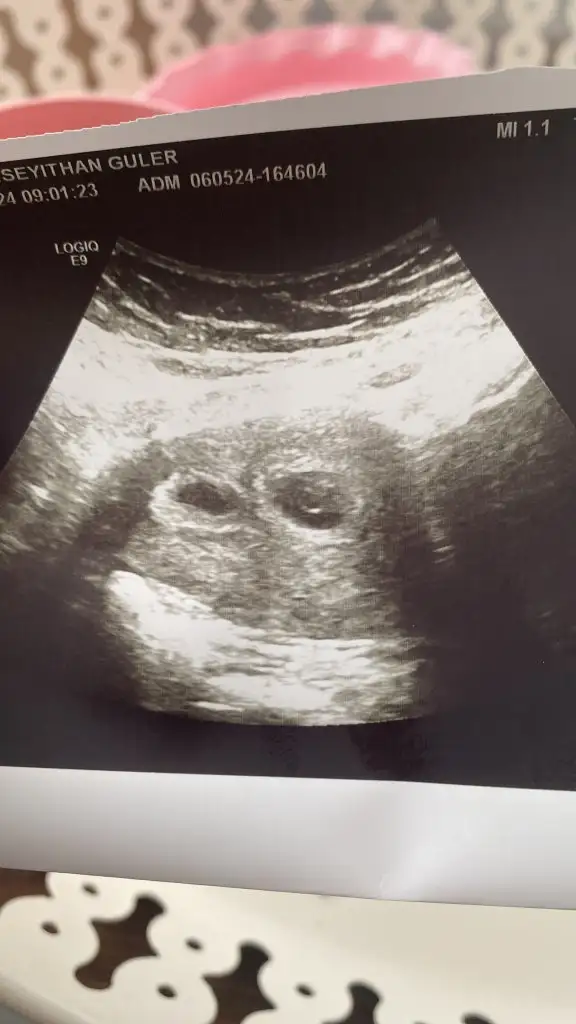

Kızlar merhaba bende geçen hafta öğrendim ikiz olduğunu bugün doktora gittim birinin kalp atışını duyduk ama diğerinin duyulmadı kesede küçük arada fark var doktor iyi de söyledi kötü de söyledi böyle bir şey yaşayan var mı keselerin fotoğrafı da bu

6 hafta 5 günlük doktor geçen haftaya göre kese gelişmemiş dedi başka bir doktora gittim kalp atışını görünüyor gibi ama küçük dedi öyle işte beklemedeyim dua edin inşallah ikisi de hayırlısı ile kucağıma gelir